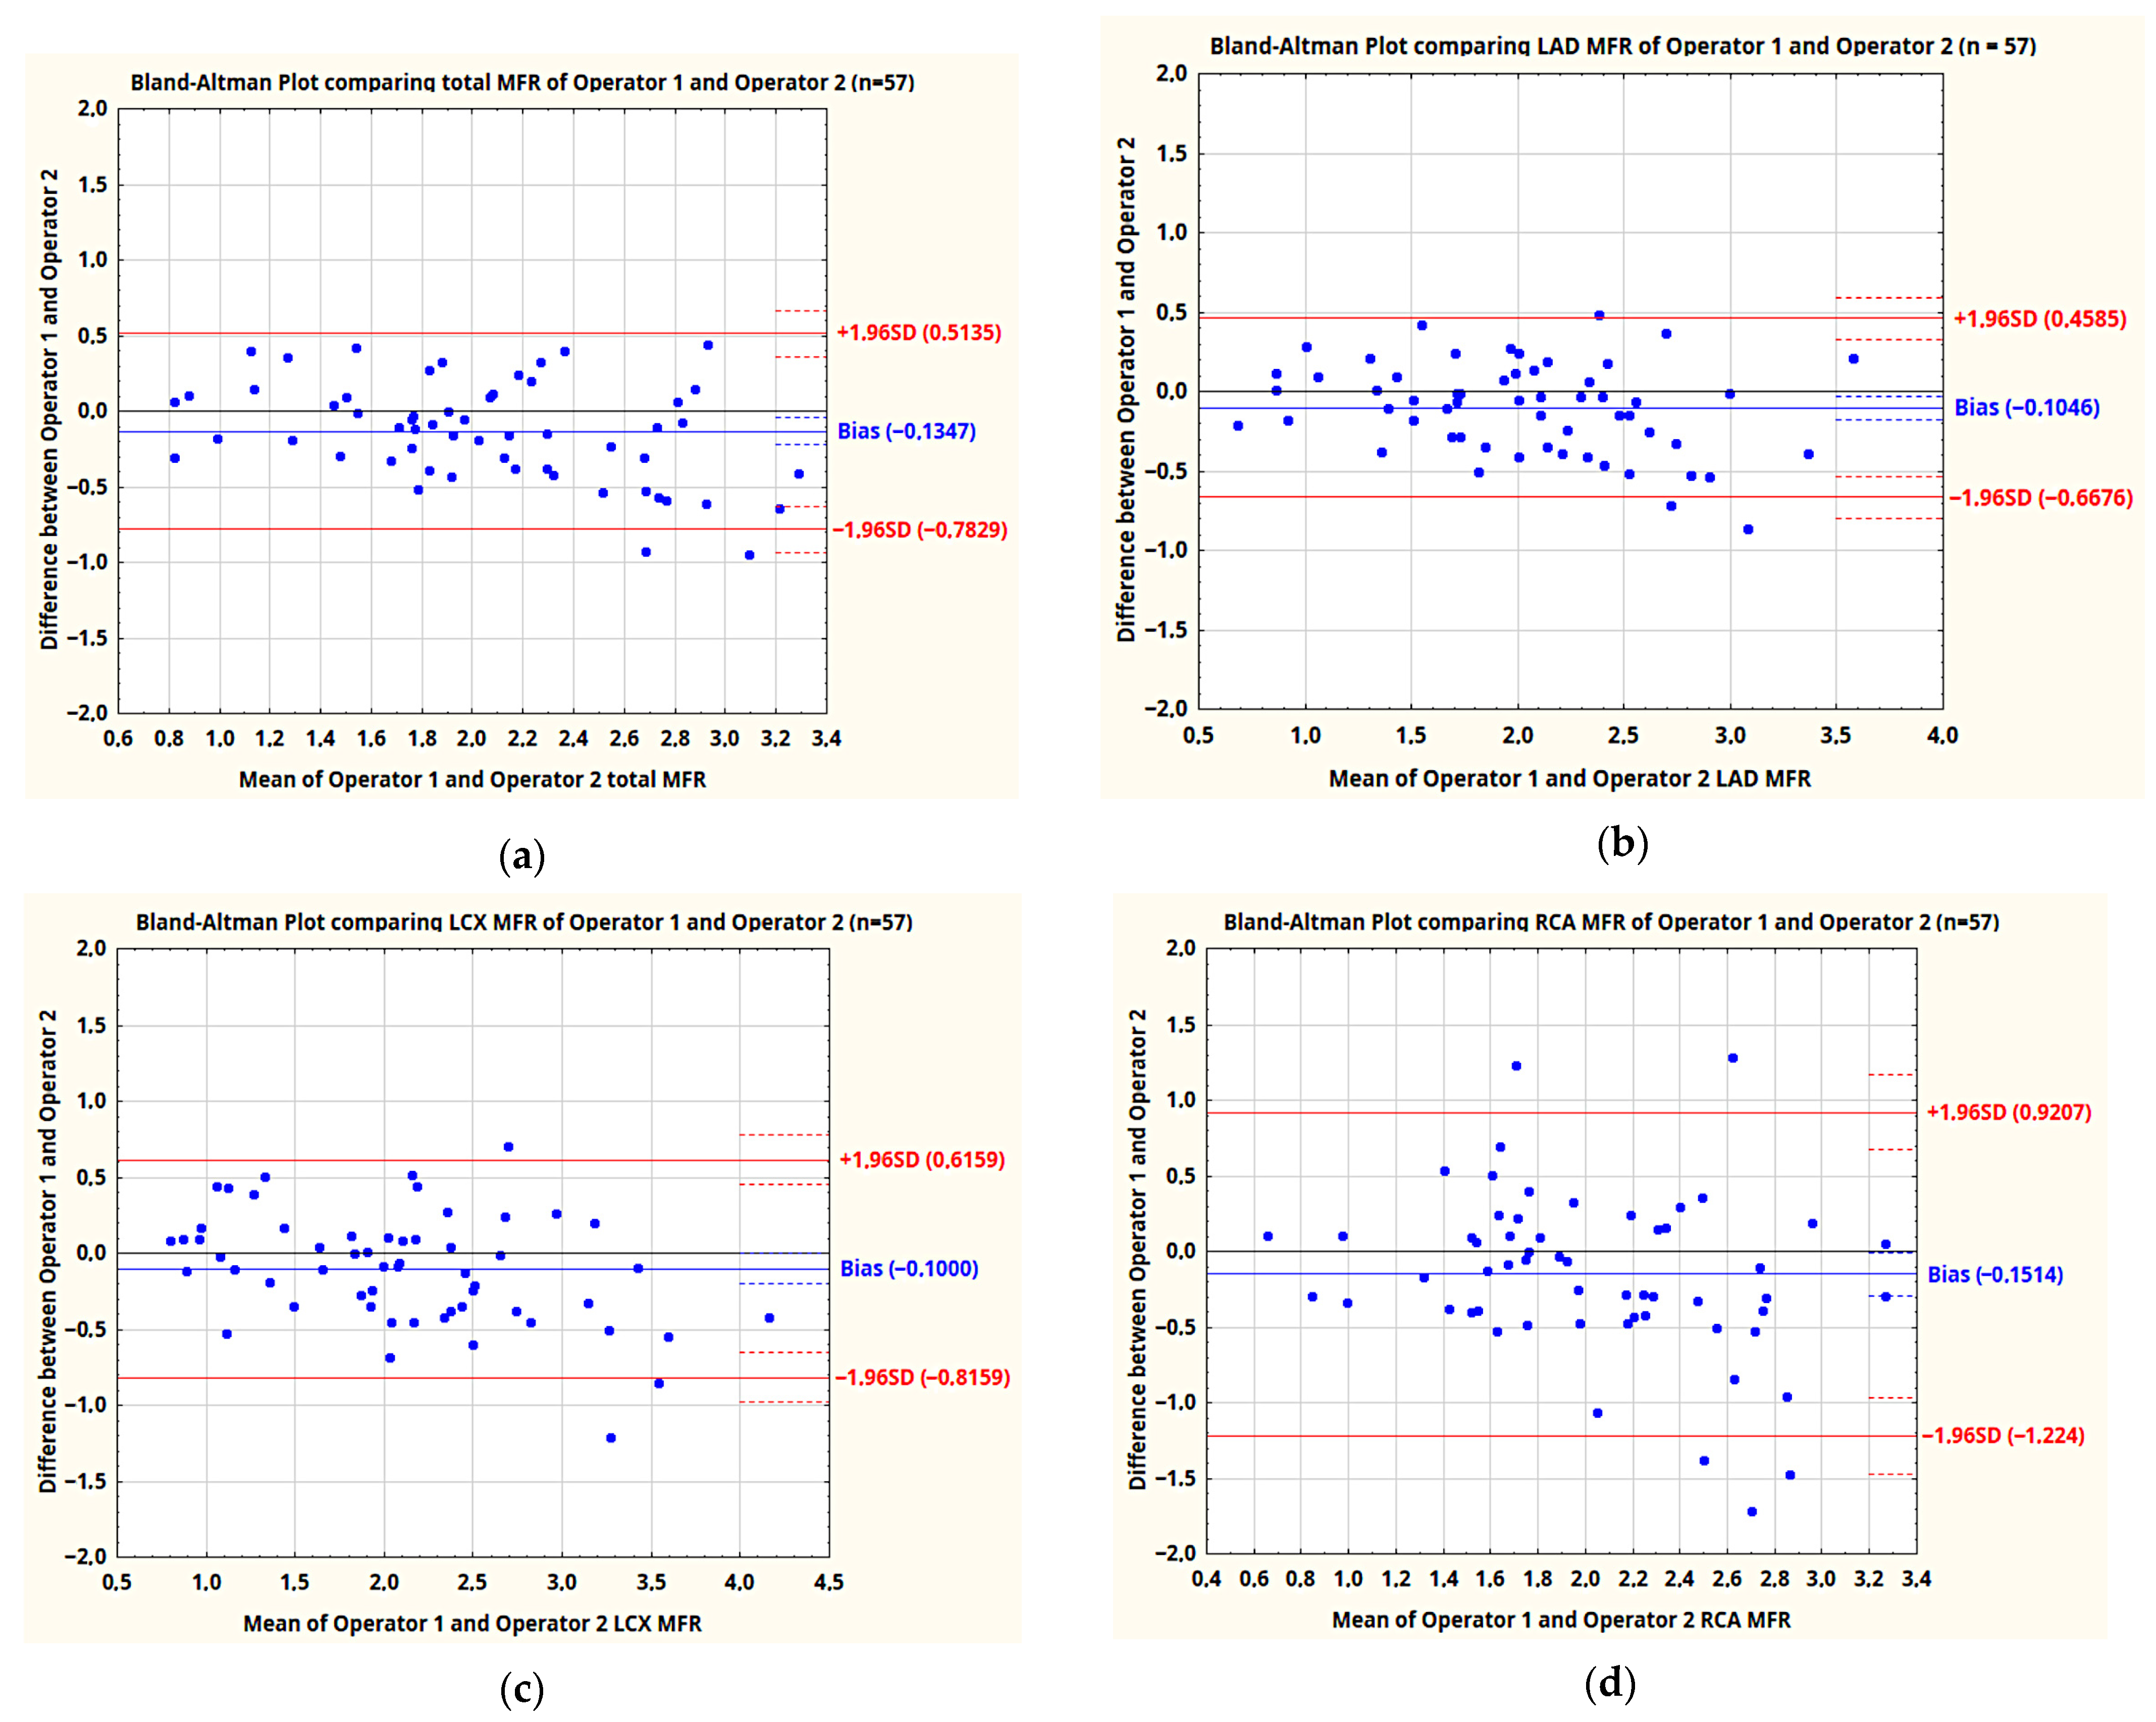

4. Discussion

| Operators | TOT | LAD | LCX | RCA | RCA vs. LAD | RCA vs. LCX | RCA vs. TOT | |

|---|---|---|---|---|---|---|---|---|

| MFR | 1 | 0.92 | 0.88 | 0.91 | 0.84 | p = 0.42 | p = 0.11 | p = 0.06 |

| 2 | 0.89 | 0.91 | 0.90 | 0.67 | p = 0.0003 | p = 0.0008 | p = 0.0019 | |

| Mean difference of MFR | 0.13 | 0.10 | 0.10 | 0.15 | ||||

| SD of difference | 0.33 | 0.29 | 0.37 | 0.55 | p < 0.0001 | p = 0.0036 | p = 0.0002 | |